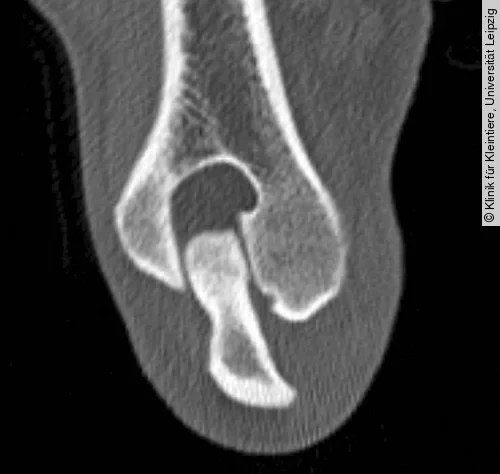

In der kraniokaudalen oder der schrägen Aufnahme fällt zunächst eine konkave beziehungsweise halbmondförmige Aufhellung des distalen medialen Humeruskondylus auf. Im späteren Stadium wird ein ausgedehnter Defekt mit subchondraler Sklerose sichtbar (Abb. [ 4 ]). Des Weiteren kann eine Abflachung der kranioventralen Fläche der Trochlea humeri dargestellt werden. Eine isolierte Schuppe, entsprechend der OCD im Schultergelenk, ist fast nie zu erkennen [15], [18], [22]. Sollte die OCD in der Projektionsradiografie nicht eindeutig zu diagnostizieren sein, sind weitere Untersuchungsverfahren wie die Computertomografie (Abb. [ 5 ]), die Magnetresonanztomografie oder die Arthroskopie zur Sicherung der Diagnose heranzuziehen [18].

Zur besseren Diagnosesicherung, vor allem bei Verdacht auf kleinere Läsionen im Bereich des Kniegelenks, bietet sich die Computertomografie an (Abb. [ 7 ], Abb. [ 8 ]) [18].